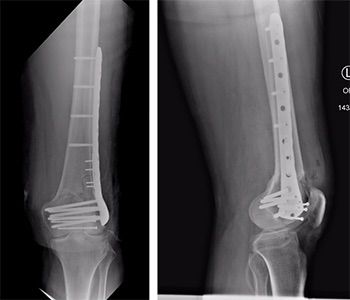

Robotic assisted knee surgery procedure image 2 Robotic assisted knee surgery procedure image 3 Robotic assisted knee surgery procedure image 4 Robotic assisted knee surgery procedure image 5

In Knee Fracture Surgery, this technology helps:

• Map the patient’s anatomy in detail

• Plan exact implant placement or fixation

• Execute surgery with millimeter-level accuracy

3. Cases Requiring Implant Placement

When plates, screws, or joint replacements are needed, robotic guidance helps in:

• Optimal positioning

• Reduced chances of implant failure

• Better long-term outcomes